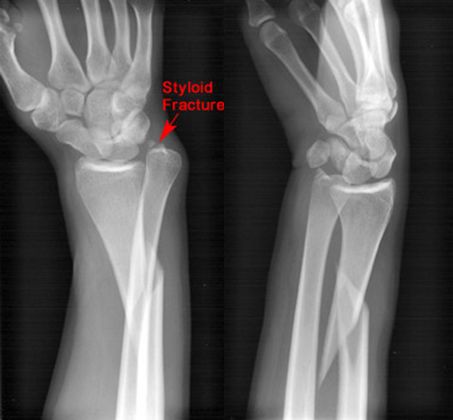

Colles骨折

• 桡骨远端骨折

• 骨折向掌侧成角

• 远折端向背侧移位

正常腕关节